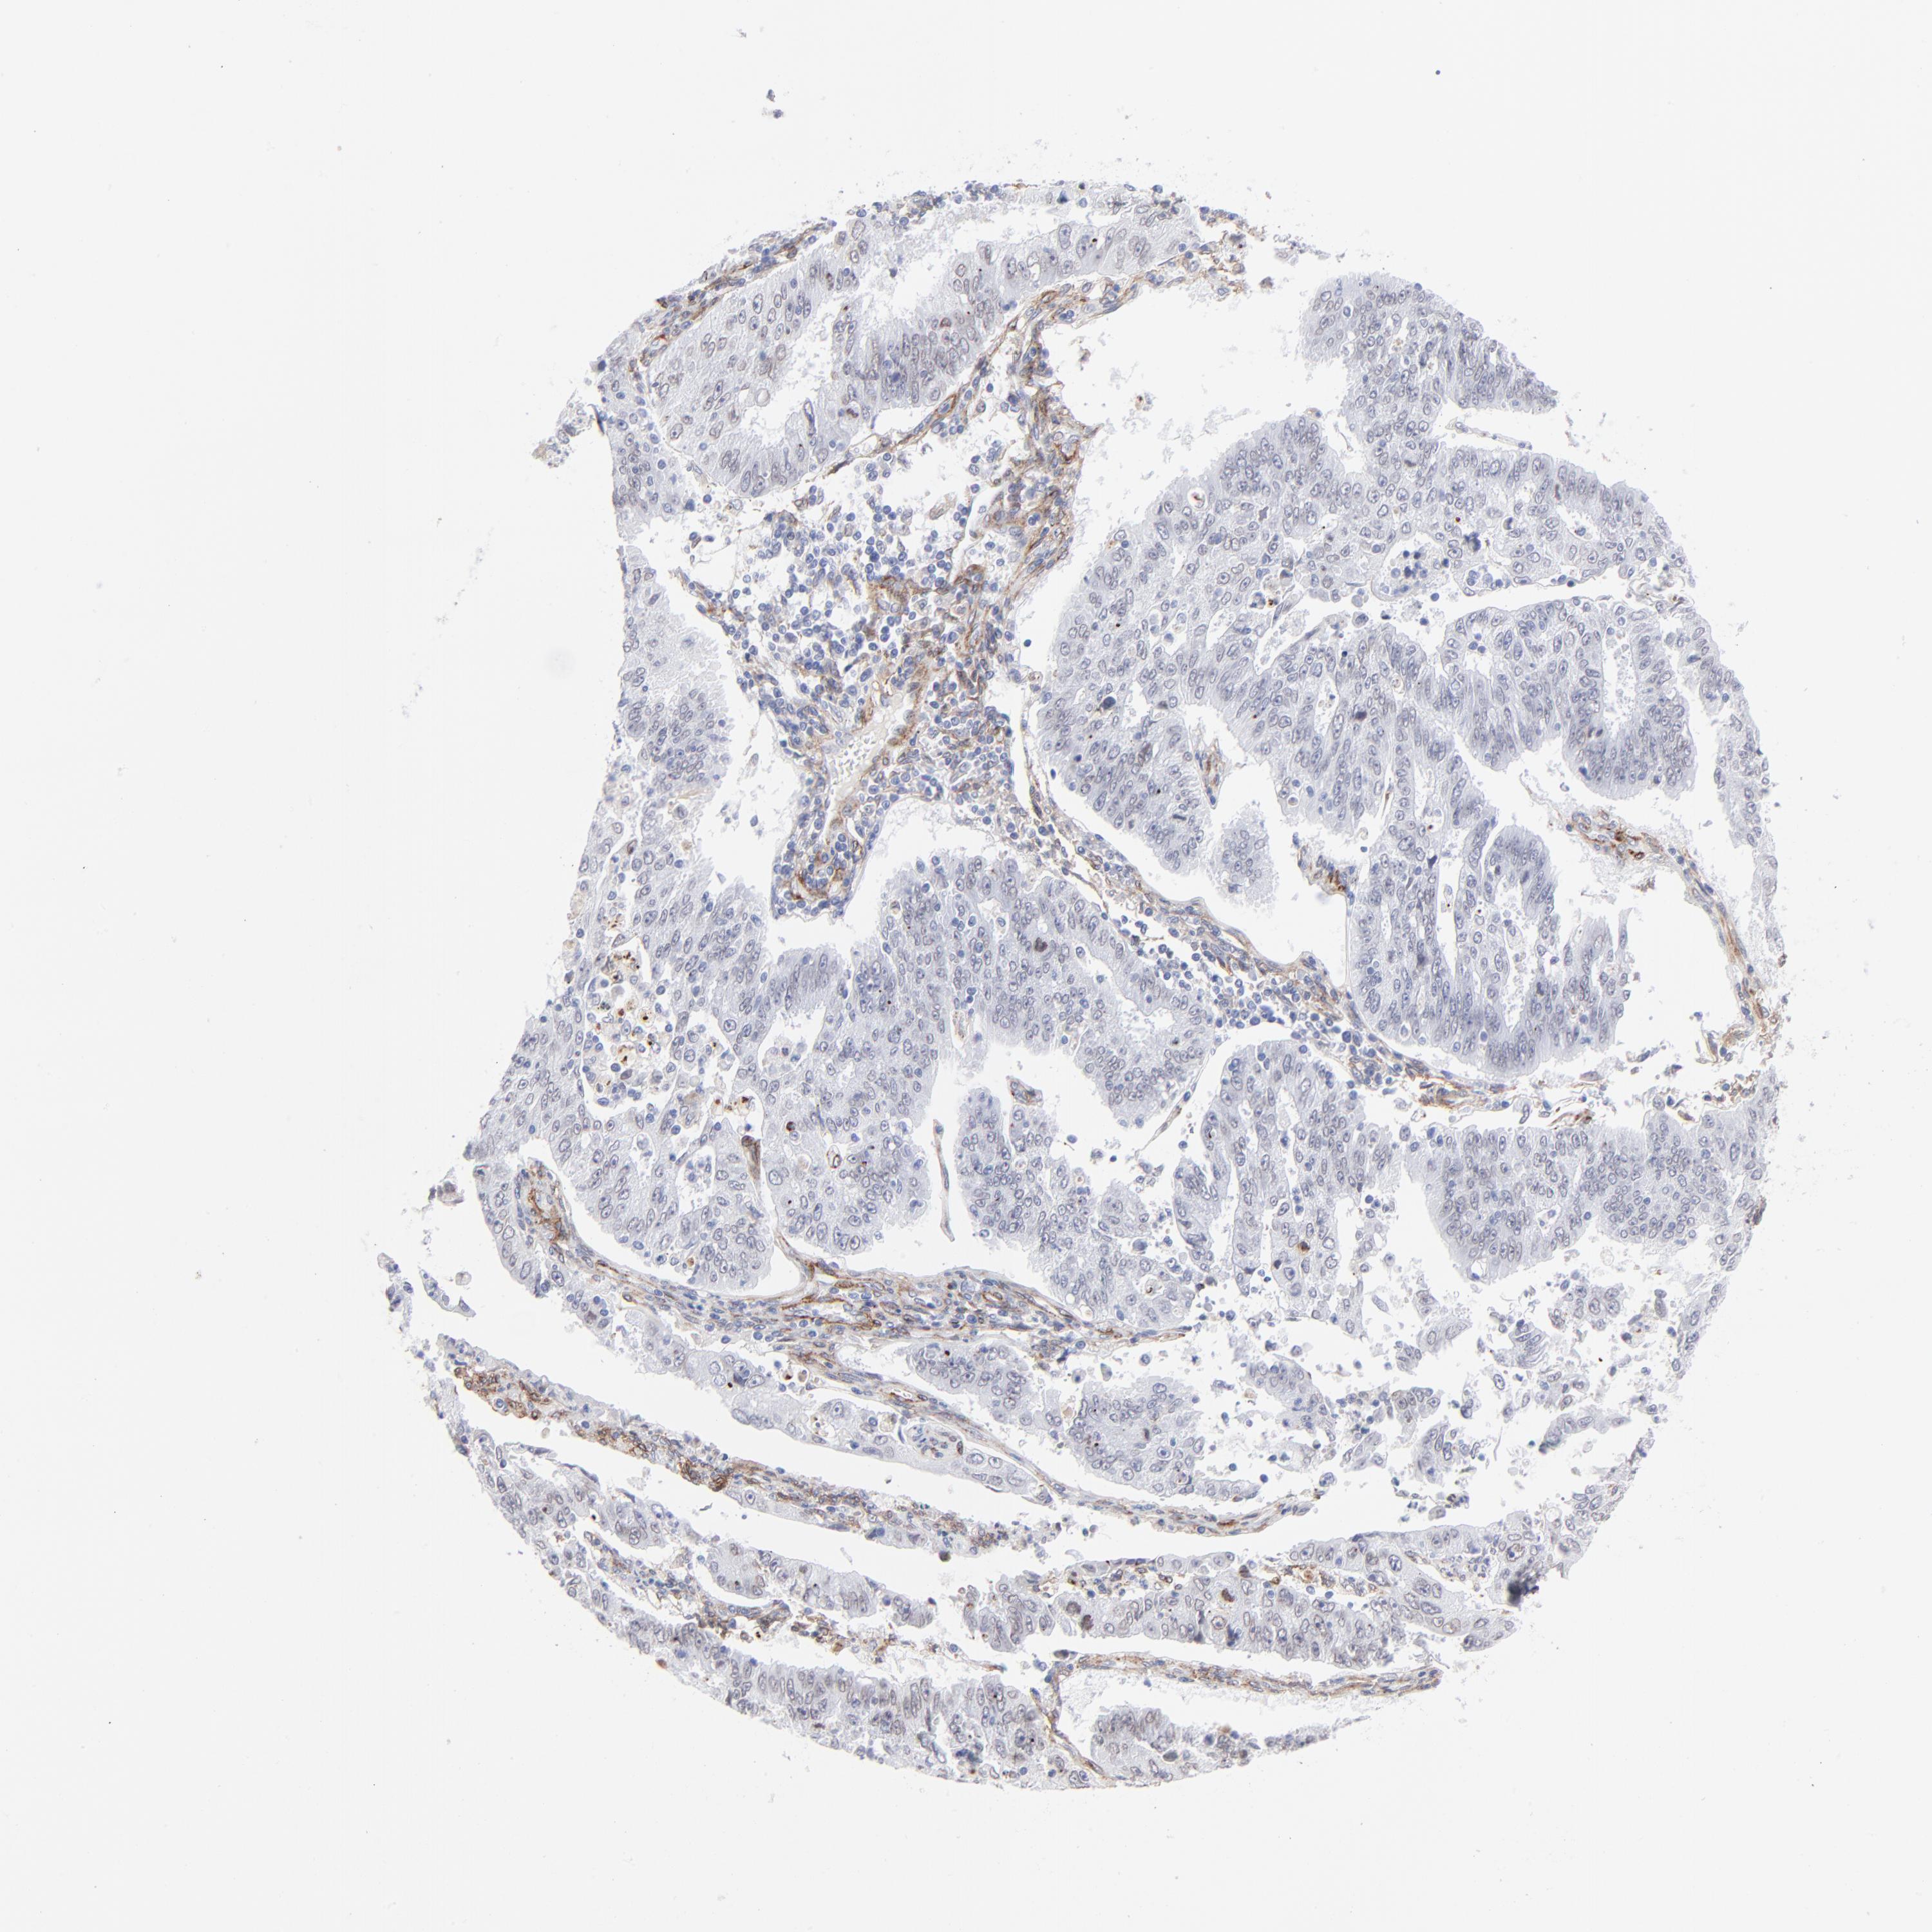

ENDOMETRIAL CANCER - Protein expressioni

A mouse-over function shows sample information and annotation data. Click on an image to view it in a full screen mode. Samples can be filtered based on level of antibody staining by selecting one or several of the following categories: high, medium, low and not detected. The assay and annotation is described here.

Note that samples used for immunohistochemistry by the Human Protein Atlas do not correspond to samples in the TCGA dataset.

Antibody stainingi

Antibody staining in the annotated cell types in the current human tissue is reported as not detected, low, medium, or high, based on conventional immunohistochemistry profiling in selected tissues. This score is based on the combination of the staining intensity and fraction of stained cells.

Each image is clickable and will lead to virtual microscopy that enables deeper exploration of all samples and also displays staining intensity scores, fraction scores and subcellular localization as well as patient and tissue information for each sample.

Antibody CAB003842

Antibody CAB018144

Staining

High

Medium

Low

Not detected

Intensity

Strong

Moderate

Weak

Negative

Quantity

>75%

75%-25%

<25%

None

Location

Nuclear

Cytoplasmic/membranous

Cytoplasmic/membranous,nuclear

Adenocarcinoma, NOS

Neoplasm, malignant, NOS

Adenoma, NOS